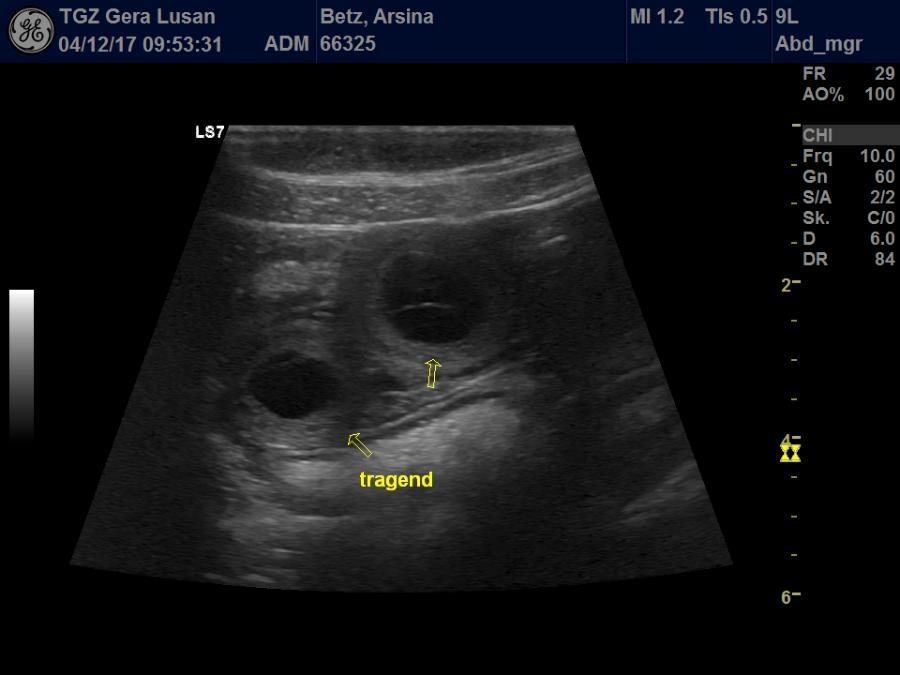

copyright Deutsche Doggen von Betz’ens Meute Hallo Fanta, ich war zur Sicherheit zweimal bei meiner Frauenärztin. Bisher ist alles in Ordnung und ein paar schöne Bilder habe ich auch bekommen. Die Ultraschallbilder vom 22. Tag sagen noch nicht viel aus, aber bei der Röntgenauf- nahme vom 48. Tag kannst du selber nachzählen wie oft Du mit einem Mal getroffen hast.